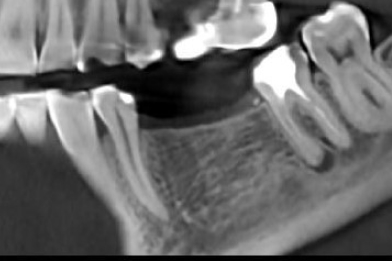

Опыт работы более 3 лет. Внимательный, вежливый доктор, специализируется на хирургической стоматологии. Лечит различные патологии челюсти: кисты, воспалительное заболевания ЧЛХ, удаляет сложные ретинированные зубы мудрости. Осуществляет дентальную имплантации, используя различные методики восстановления костной ткани.

- Имплантация зубов

- Удаление зубов

- Удаление зуба мудрости